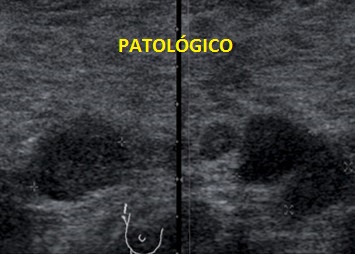

Te pido ahora que observes aténtamente la imagen 7 y la imagen 8 y en las lesiones marcadas con flechas amarillas. En la imagen 7 puedes ver imágenes nodulares en ambos lóbulos tiroideos, son nódulos de los que habitualmente encontramos en un bocio multinodular, compara ahora con la imagen de la imagen 8, así a bote pronto, ¿Te llama algo la atención?…mira bien las imágenes…tómate un momento, no sigas leyendo…

Sí, efectivamente, la lesión de la imagen 8, que es a la que le hemos estado dedicando este tiempo, parece estar localizada fuera del tiroides, en su LTD, concretamente en su porción más profunda, como pegada a él…aunque el aspecto pueda ser similar a un nódulo normal, en este caso, la localización de la lesión, también nos va a ayudar en el diagnóstico.